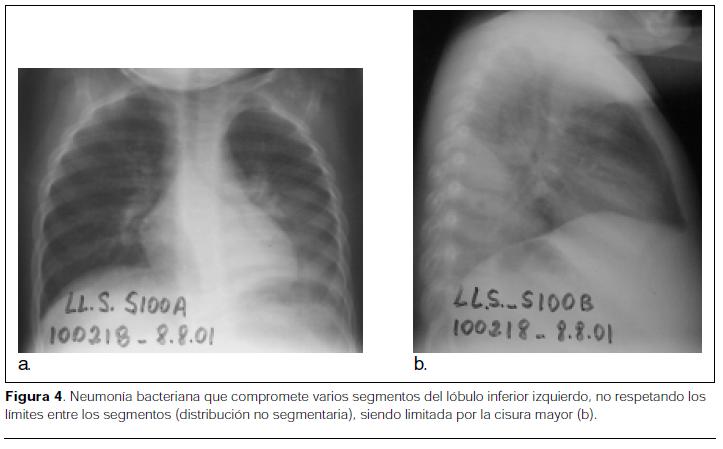

- Distribución no segmentaria: la infección en la neumonía bacteriana, por su forma de propagación, no respeta los límites entre los segmentos (distribución no segmentaria)(figuras 4, 5 y 6) (1,8).

- Progresión: la consolidación de la neumonía comienza generalmente en el parénquima subpleural. Típicamente se observa una opacidad pulmonar que progresa en dirección centrífuga desde un centro subpleural y puede afectar uno o varios segmentos de un mismo lóbulo o de lóbulos pulmonares diferentes, pudiendo comprometer los segmentos pulmonares de manera parcial o completa; lo más frecuente es que la enfermedad se limite a un solo lóbulo, pero en ocasiones la infección tiene lugar simultáneamente en dos o más (figuras 5, 6 y 7).

La progresión de la infección bacteriana es limitada por la pleura visceral, otorgándole a ese nivel un borde bien definido, permitiendo realizar diagnóstico topográfico del foco (figuras 8 y 9) (1,8,10-16). - Carácter del borde: es también un elemento semiológico radiológico de valor, en el momento del establecimiento de un diagnóstico causal probable. La neumonía con consolidación de los espacios aéreos, que se ha extendido por una superficie pleural interlobular posee un contorno definido (figura 5b). En las zonas donde no contacta con una cisura, su límite no es nítido. Éste queda determinado por una zona irregular de lesiones acinosas confluentes correspondientes al pulmón consolidado y el parénquima contiguo normal que contiene aire (figura 5a) (8).